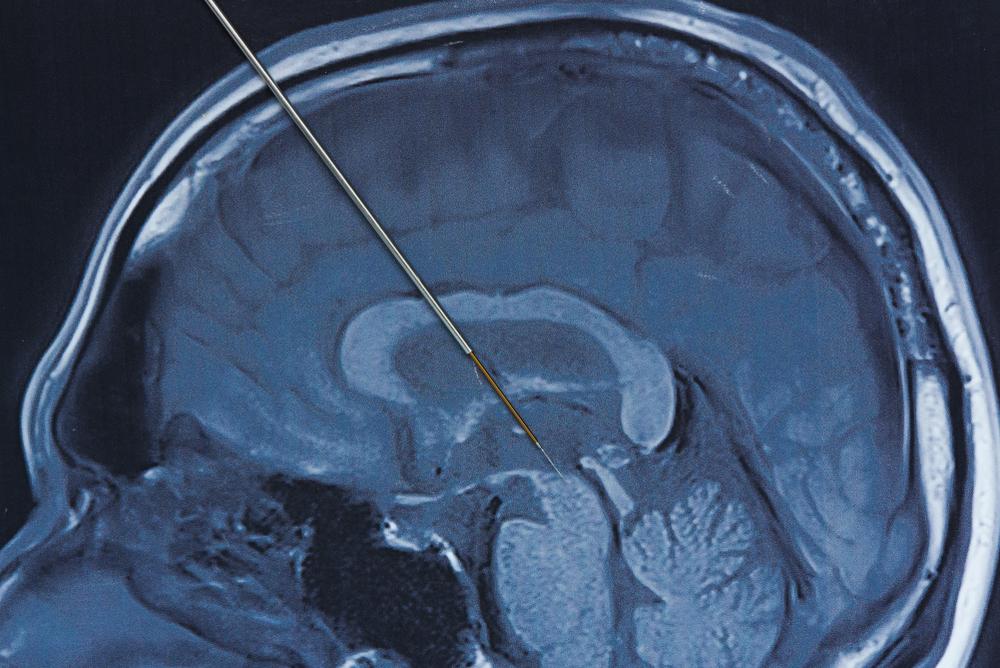

Deep brain stimulation (DBS) atau stimulasi otak dalam adalah prosedur bedah saraf yang menggunakan perangkat implan elektroda dan stimulasi listrik di otak.

Elektroda ini ditanam di dalam otak untuk menghasilkan impuls listrik.

Impuls tersebut dapat mengontrol aktivitas listrik yang abnormal di otak atau memengaruhi sel dan zat kimia tertentu di dalamnya.

- Menggunakan MRI atau CT scan kepala untuk mencari area otak yang akan ditanam implan.

- Memasukkan kawat tipis melalui sayatan dan lubang kecil di tengkorak tersebut dengan implan elektroda yang berada di ujungnya.